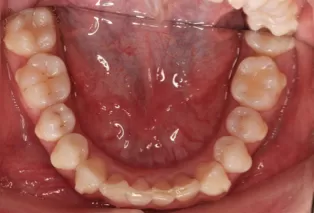

Photos intra-orales après traitement